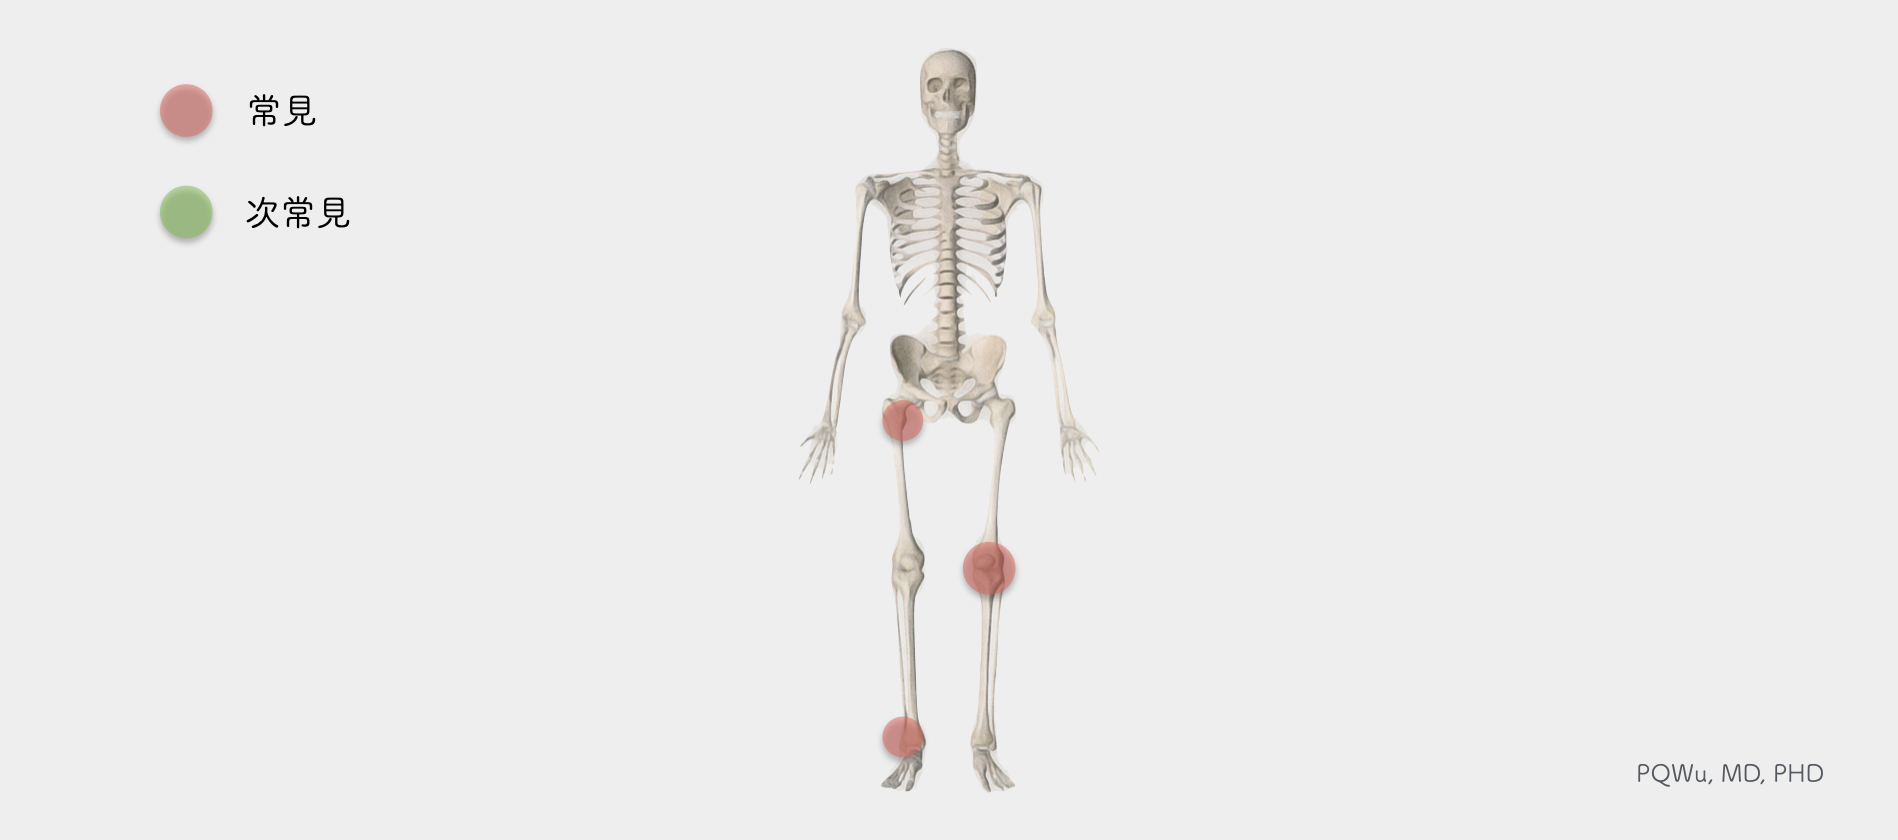

腱鞘巨細胞瘤(色素絨毛結節性滑膜炎)最常發生於膝關節,大約佔50%。其他常見的位置,包括髖關節(約20%)與踝關節(10%),少部分的色素絨毛結節性滑膜炎會發生在顳顎關節(Temporomandibular joint, TMJ) 與脊椎。基本上,僅發生在一個關節,並不會多個關節同時發生。